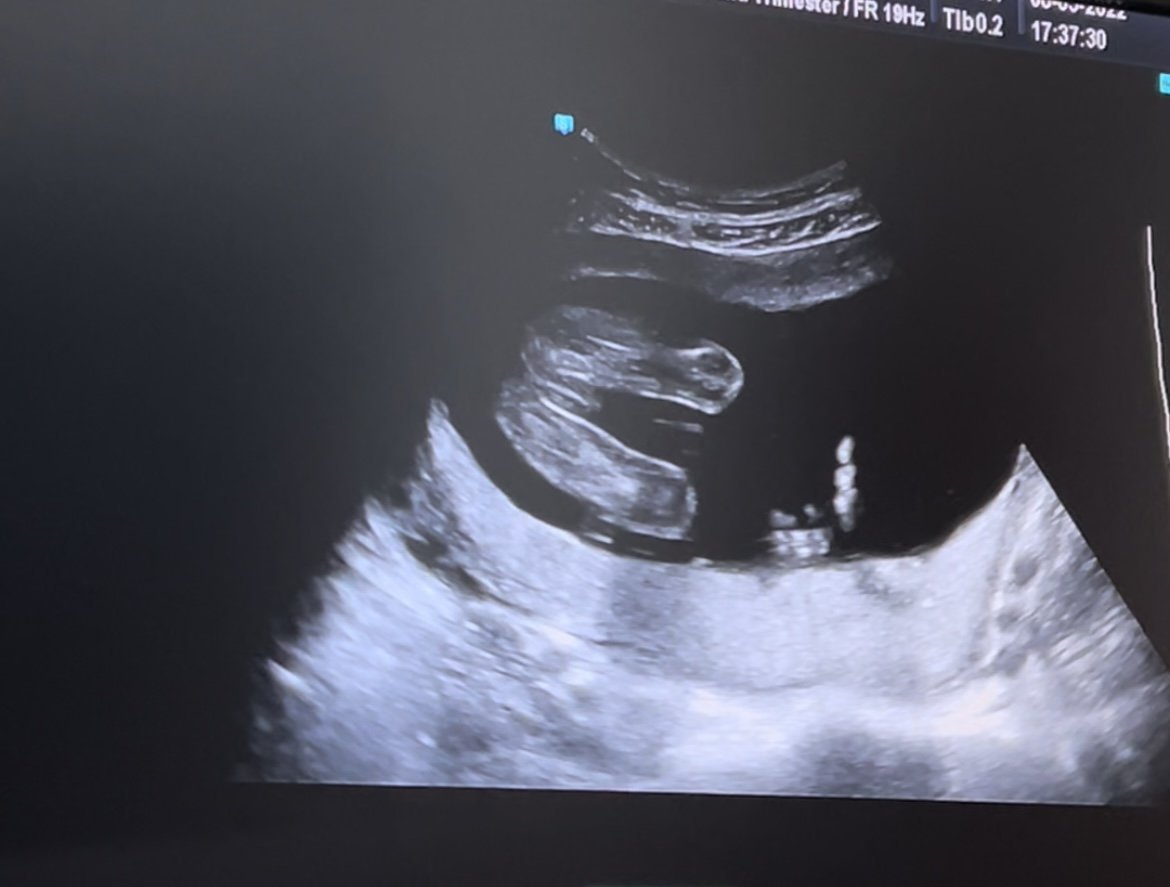

Здравейте ,доктора ми каза че очакваме момиченце ,но все пак прикачвам снимка и ще се радвам да ми кажете на вас на момиченце ли ви прилича😁Благодаря предварително.

Момиченце е, да. Честито 🤗

Имаме подобна снимка на дъщеря ми.☺

По момичешко от това, няма накъде. Честито, живо и здраво бебче, нека изпълни с радост дома ви.

Прилича ми на бебе, момиче, момче живо и здраво да е, по важно от това няма.